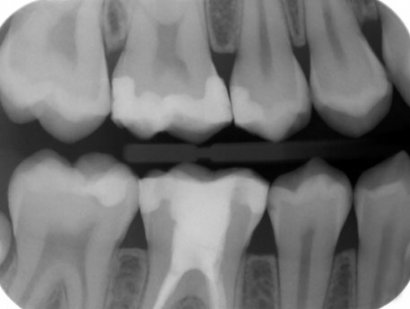

RX. Periapicales

RX. Bitewing